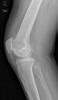

APR Gonartrosis

Prótesis completa de rodilla. Situación postquirúrgica.

Prótesis completa de rodilla. Situación postquirúrgica. Lateral.

Prótesis completa de rodilla.Lateral.

Prótesis completa de rodilla. Frontal.

Prótesis completa bilateral de rodillas.

Prótesis completa de rodilla. Perfil.

Prótesis completa de rodilla. Frente.